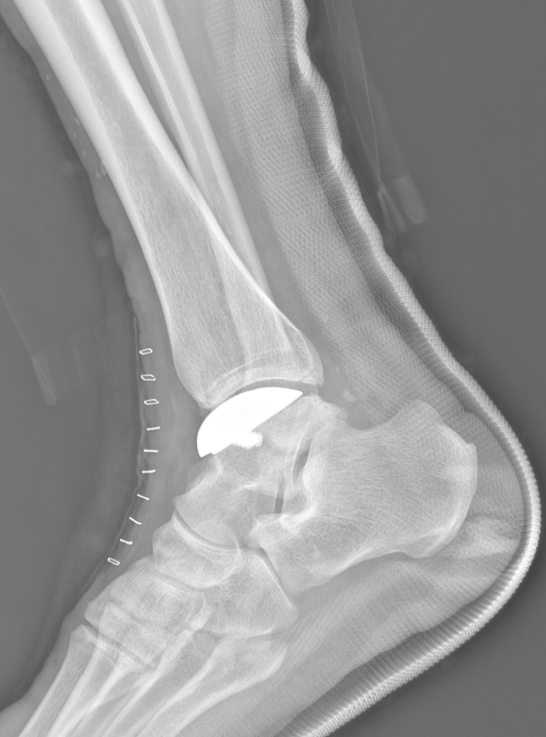

术前踝关节侧位X线

术后侧位X线